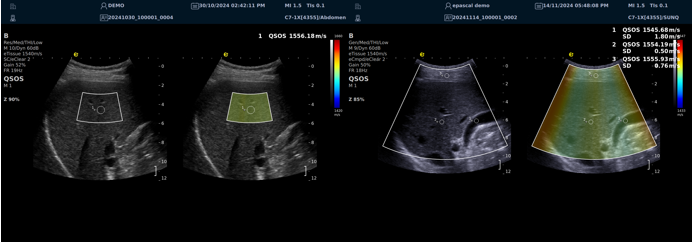

RTE实时弹性成像

?肌骨系统组织的硬度可反应炎症的严重程度?肌肉肌腱组织进行弹性测定,有助于检测创伤性及退变性病变?肌肉肌腱炎性程度评估?精准定位肌痛点?治疗前后功能疗效评估

RTSWE实时剪切波弹性成像

?探头发射激励脉冲进行多点动态聚焦,利用马赫圆锥原理,形成大量的剪切波信号?颜色的变化与剪切波的速度相关,可直接体现肌肉肌腱等组织硬度值?实时、全幅、全定量

鉴别诊断、精准分级、定量评价、穿刺引导、疗效评估、随访观察

ATI高级声衰减成像

?独有的幅度损失的衰减方法ALA,准确性高,稳定性好,实时性好?业界唯一支持凸阵与线阵两种探头?支持多个取样框?提供两种显示单位

肌骨领域的应用

?肌腱炎症或损伤的评估?肌肉拉伤的定位?关节磨损或炎症的诊断?骨质疏松的早期发现和监测

QSOS声速定量成像

QSOS技术采用彩色编码显示声速图像,不同颜色代表不同声速值,便于医生识别病变部位和测量。

?精准定量反映组织特性,成像更敏锐?彩色编码直观显示,轻松发现异常?捕捉声速差异,早期、微小病变更易察觉

肌骨领域的应用

?精准定位损伤部位?判断损伤严重程度?监测肌肉营养?评估肌少症?骨质疏松评估